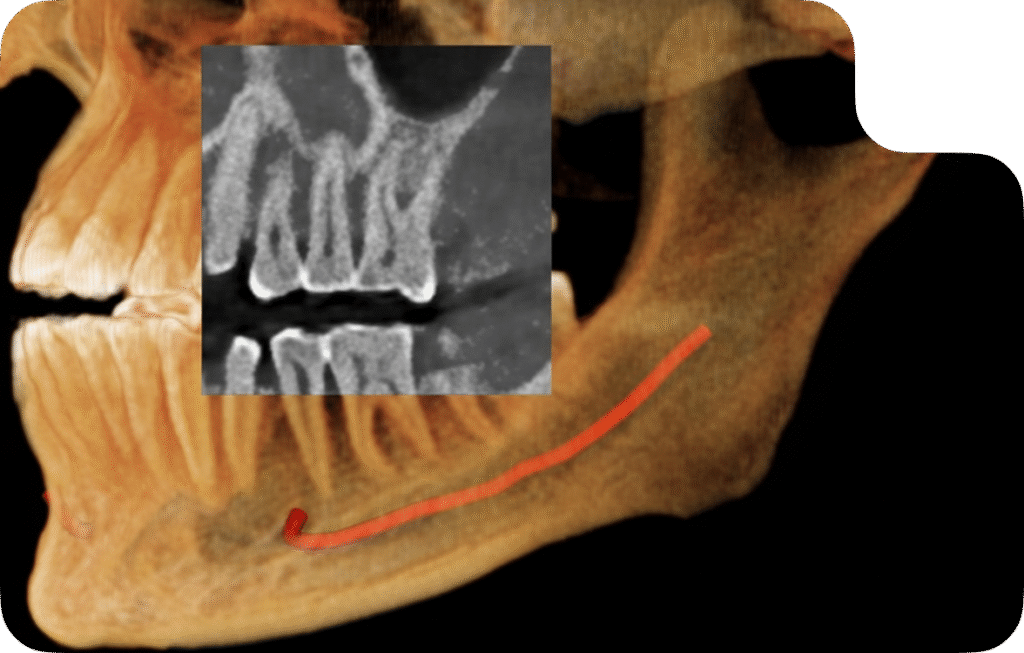

3D Imaging – Cone Beam Computed Tomography (CBCT)

CBCT scans provide a complete 3D view of teeth, bone, and jaw anatomy, crucial for complex dental cases. Dentists rely on CBCT for implant placement, endodontic therapy, orthodontic evaluations, TMJ analysis, and oral surgery. With detailed anatomical visualization, we give clinicians the confidence to achieve predictable and successful outcomes.

3D Imaging - CBCT